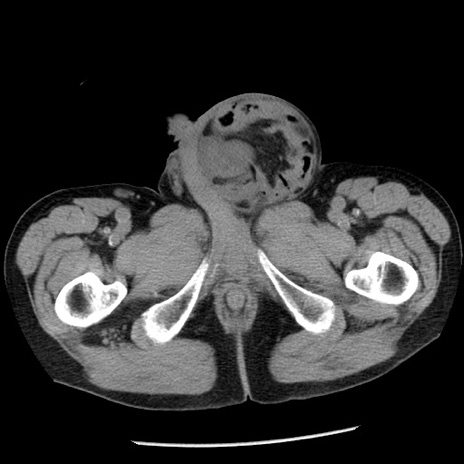

症例26(横断像)

【症例】80歳代男性

【主訴】嘔吐

【現病歴】昨晩2回嘔吐あり、今朝になっても嘔吐あり。来院。

【既往歴】胃潰瘍

【身体所見】意識清明、BT 37.6℃、BP 166/95mmHg、HR 100bpm、SpO2 97%、腹部:平坦・軟、腸蠕動音聴取良好、圧痛なし。

【データ】WBC 21900、CRP 1.46